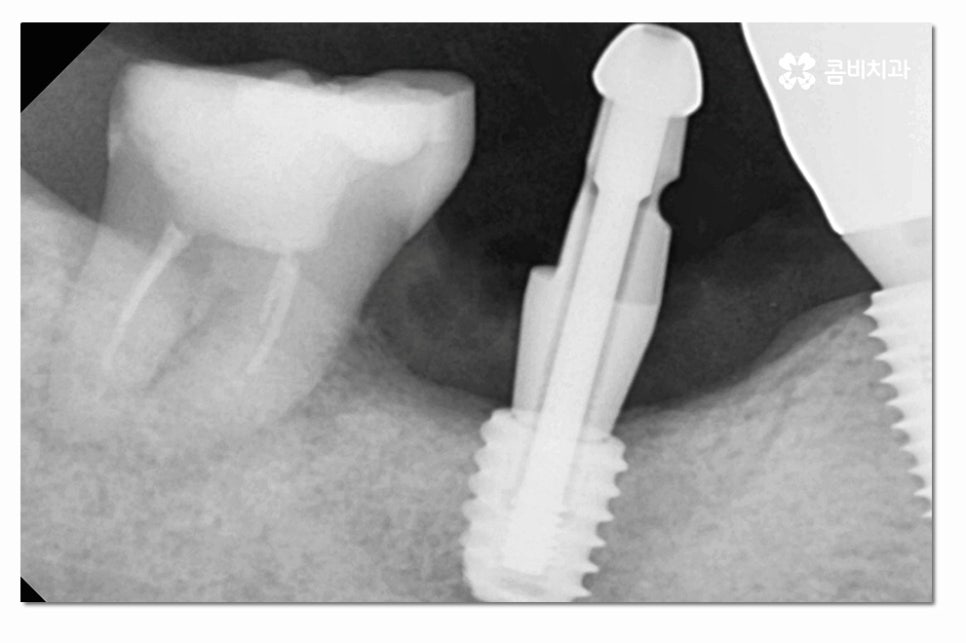

위 사진처럼 어금니를 발치한 후에는 잇몸이 차오르길

기다리게 되고 임플란트를 식립할 잇몸 뼈가

충분한지 잇몸 상태를 정밀 검진을 통해 확인하는 과정을

거치며 잇몸이 부족한 경우에는 뼈이식을 받아야 할 수 있어요.

어금니임플란트의 경우 심미성보다는 기능성에 보다 집중된

치료가 이뤄지게 되는데 요즘은 3D CT 등을 통해

정확도 높은 진단이 이뤄지고 있지만 시술은 의사의 경험과

실력이 중요한 부분이기 때문에 어금니임플란트는

특히 저작기능을 수행하는 데 유리한 식립 각도와

위치 선정을 잘하는 것이 중요하다고 할 수 있어요.